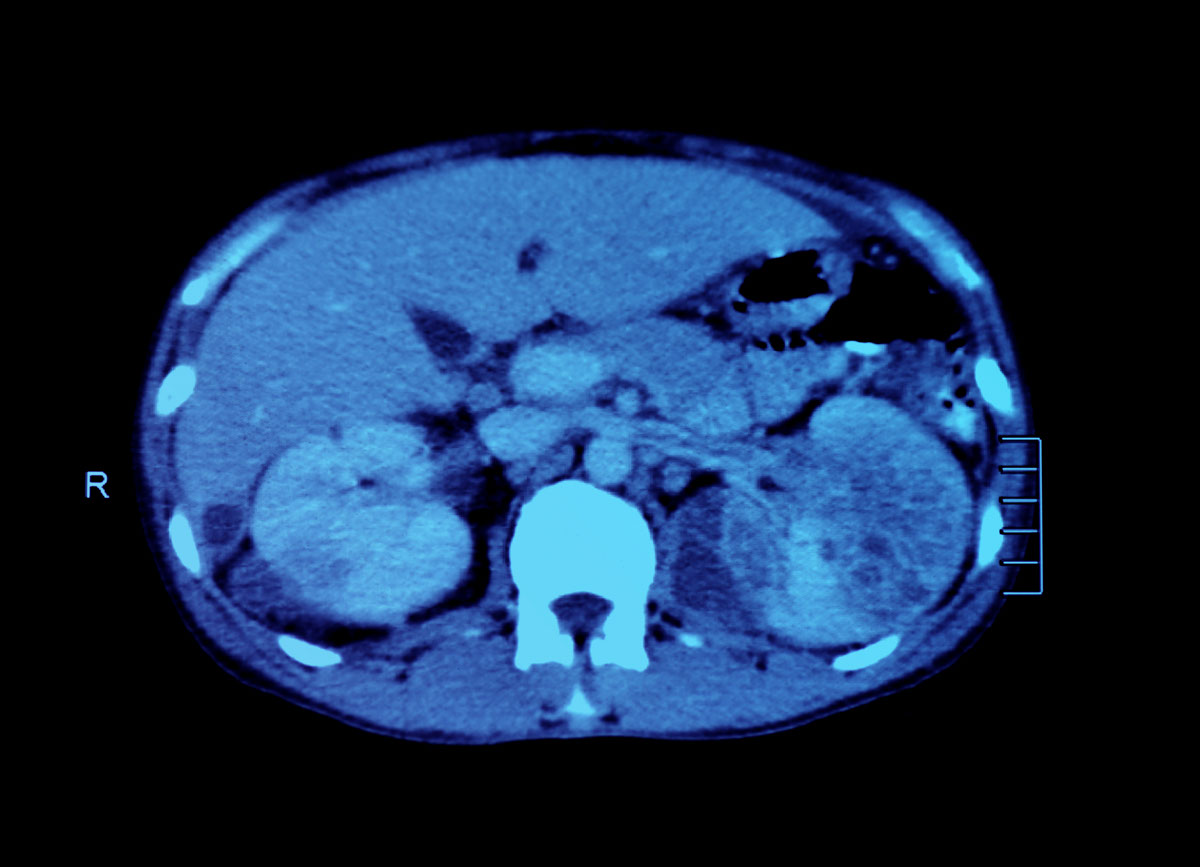

(2) 電腦掃描 (computed tomography)

冷凍消融技術可在超聲波、電腦掃描、磁力共振等影像學引導下進行,也可通過腹腔鏡完成。